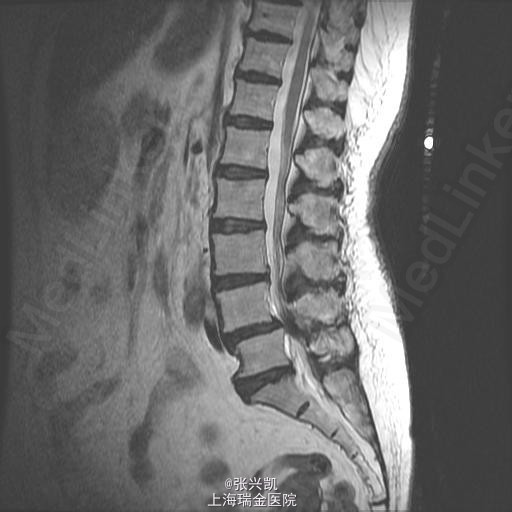

查体:脊柱无侧弯畸形,无叩痛压痛,上肢感觉肌力正常,双下肢疼痛,右侧较重,小腿前外侧感觉异常,下肢肌力4-5级,跟膝腱反射(+),巴氏征(-) 辅助检查:X线动力位示:L4椎体滑脱,腰椎退行性改变 MR:L4椎体向前I°滑脱,L3-5椎间盘突出,椎管狭窄

诊断:腰椎椎管狭窄L4-5 L4椎体滑脱 处理:腰椎后路减压复位融合内定术